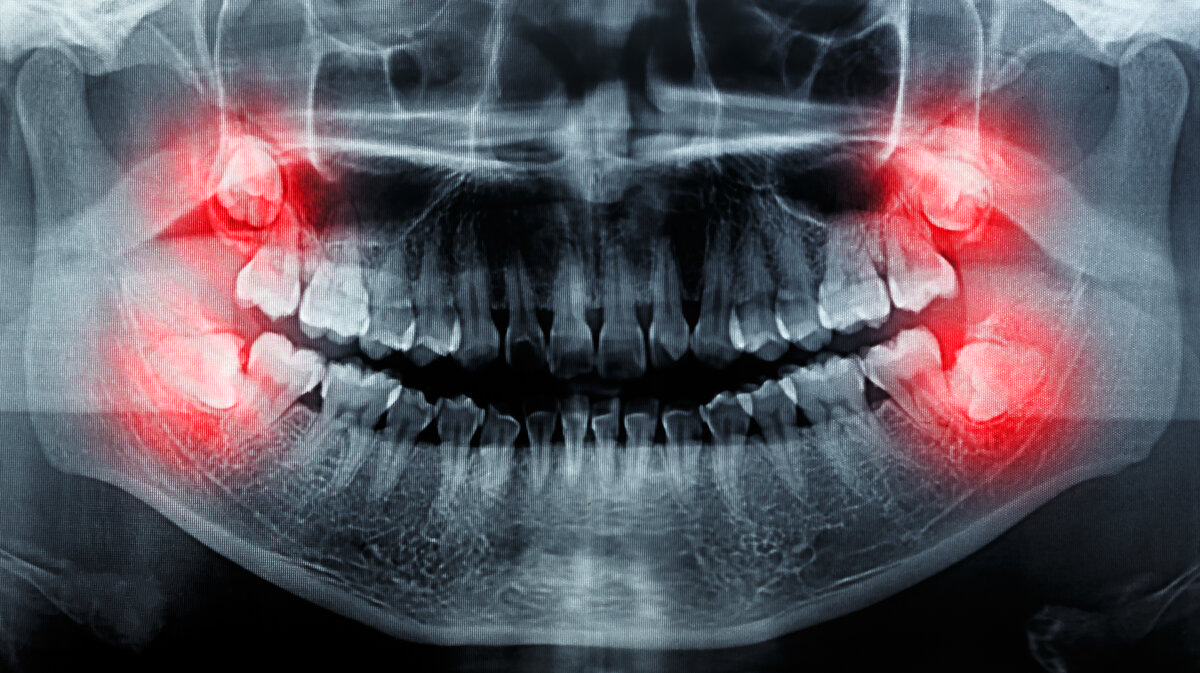

Зубы мудрости, или «восьмёрки», являются частью нашего зубного ряда, которая обычно начинает прорезываться в возрасте от 17 до 25 лет. Однако, несмотря на то что эти зубы считаются последними по времени появления их у человека, иногда они могут проявиться и в более позднем возрасте. Существуют случаи, когда люди старше 30-40 лет обнаруживают новые зубы мудрости.

Один из самых удивительных случаев был зафиксирован у 94-летнего мужчины, у которого прорезалась «восьмёрка». Это вызывает интерес специалистов стоматологии и подтверждает гипотезу о том, что зубы мудрости действительно могут вырасти в любом возрасте. Давайте рассмотрим этот феномен подробнее и выясним, какие факторы могут повлиять на такое редкое явление.

Известно, что зубы мудрости обычно начинают расти в возрасте от 17 до 25 лет, однако редкие случаи показывают, что они могут проявиться и в более зрелом возрасте. Недавно был зафиксирован случай, когда у 94-летнего мужчины прорезалась восьмёрка. Этот случай поднимает вопрос о том, является ли процесс прорастания зубов мудрости мифом или реальностью. Некоторые исследования говорят, что действительно могут существовать генетические или анатомические особенности, позволяющие зубам мудрости проявиться позднее, хотя это является редким исключением. Таким образом, хотя прорастание зубов мудрости в пожилом возрасте не является типичным, оно все же возможно благодаря разнообразию факторов, включая генетику и индивидуальные особенности человека.

Зубы мудрости, известные также как «восьмерки», обычно проявляются в возрасте от 17 до 25 лет. Однако, иногда уникальные случаи демонстрируют, что эти зубы могут вырастать и в пожилом возрасте. Недавно был зафиксирован случай, когда у 94-летнего мужчины прорезалась «восьмёрка». Этот удивительный процесс может быть связан с генетикой, изменениями в полости рта или даже с жизненными обстоятельствами. Этот случай подчеркивает важность регулярного посещения стоматолога даже на пожилом возрасте, чтобы следить за здоровьем зубов и обнаруживать потенциальные проблемы своевременно.

Прорезывание зубов мудрости у взрослых является редким явлением, но не исключено. Возможность того, что зуб мудрости начнет расти во взрослом возрасте, связана с индивидуальными особенностями организма. Обычно процесс прорезывания зубов мудрости происходит в возрасте от 17 до 25 лет, но иногда может наблюдаться и в более поздние сроки. В случае с 94-летним мужчиной, который родился в 1920-х годах, прорезалась «восьмёрка», что демонстрирует, что жизнь и организм каждого человека уникальны. Появление зубов мудрости в пожилом возрасте может вызвать дискомфорт и требует внимательного врачебного контроля и ухода.

Зубы мудрости могут вырасти в любом возрасте, что подтверждает наблюдение случая, когда «восьмёрка» прорезалась у 94-летнего мужчины. Однако, влияние возраста на рост зубов мудрости может быть различным. У некоторых людей они начинают прорезываться уже в юном возрасте, в то время как у других процесс прорезывания может затянуться на десятилетия. Это связано как с индивидуальными особенностями организма, так и с общим состоянием здоровья человека. Важно помнить, что рост зубов мудрости может вызвать болевые ощущения и проблемы с прикусом, поэтому в случае дискомфорта необходимо обратиться к стоматологу для профессиональной консультации и возможного лечения.